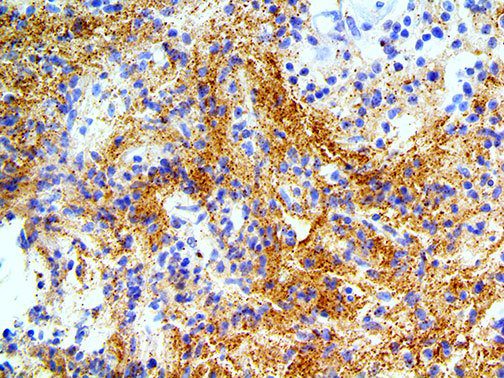

The first cytokines released are interleukin 1β (IL-1β) and tumor necrosis factor-α (TNF-α), which attract a variety of circulating white blood cells (WBCs) to the infection site, including neutrophils, monocytes, macrophages, and natural killer (NK) cells. This response, along with the antipathogenic chemicals released by these cells (i.e., complement), comprise the innate immune response. These cells directly attack the invading pathogen and also release additional cytokines, chief among them interleukin-1 and 6 (IL-6). IL-6 is essential for invoking the adaptive immune response, which calls T-cells, B-cells, and T helper (Th) cells to the infection site. IL-6 also stimulates further recruitment, proliferation and activation of macrophages.

This activation induces inflammatory monocytes to highly express IL-6, starting a localized and then systemic cascade effect that results in hyperproduction of IL-6, which accelerates the inflammatory process. Because IL-6 also increases vascular permeability, excessive levels cause blood vessels to become very leaky. This, along with clotting factors released from vascular endothelial cells, stimulates the coagulation cascade, resulting in microthrombosis (tiny clots), which leads to ischemia and tissue death of the kidney, intestines, heart, liver, brain and extremities.